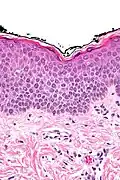

In der histologischen (lichtmikroskopischen) Untersuchung einer Gewebeprobe aus erkrankter Haut weist das Ekzem die Merkmale einer spongiotischen Dermatitis auf. Analog zum klinischen Bild zeigt sich ein charakteristischer Verlauf der Veränderungen:

Akute Phase: In der Oberhaut (Epidermis) zeigt sich eine Gefügelockerung durch ein interzelluläres Ödem (Spongiose), das bei starker Ausprägung zur Ausbildung von kleinen, aber auch größeren Blasen (Vesikel bzw. Bullae) führen kann.

Als Kratzeffekt besteht eine überschießende und eventuell auch gestörte Verhornung (Hyperkeratose bzw. Parakeratose) mit überliegender Schuppenkruste (parakeratotische Hornschicht mit eingeschlossenen Serumresten). Auch die oberen Anteile der Lederhaut (Dermis) sind durch ein Ödem gelockert, hier finden sich außerdem weitgestellte kleine Blutgefäße (Kapillaren). Um diese Gefäße bilden sich Ansammlungen aus Entzündungszellen, die sich hauptsächlich aus Lymphozyten und Histiozyten, nicht selten auch eosinophilen Granulozyten (Untergruppen der weißen Blutkörperchen) zusammensetzen. Lymphozyten wandern teilweise auch in die Epidermis ein (lymphozytäre Exozytose).

Spongiose: Gefügelockerung der Epidermis mit sichtbaren Spalten zwischen den einzelnen Zellen durch interzelluläres Ödem -

Vesikelbildung: bei starker Spongiose lösen sich die Zellen voneinander und es bilden sich kleine Bläschen